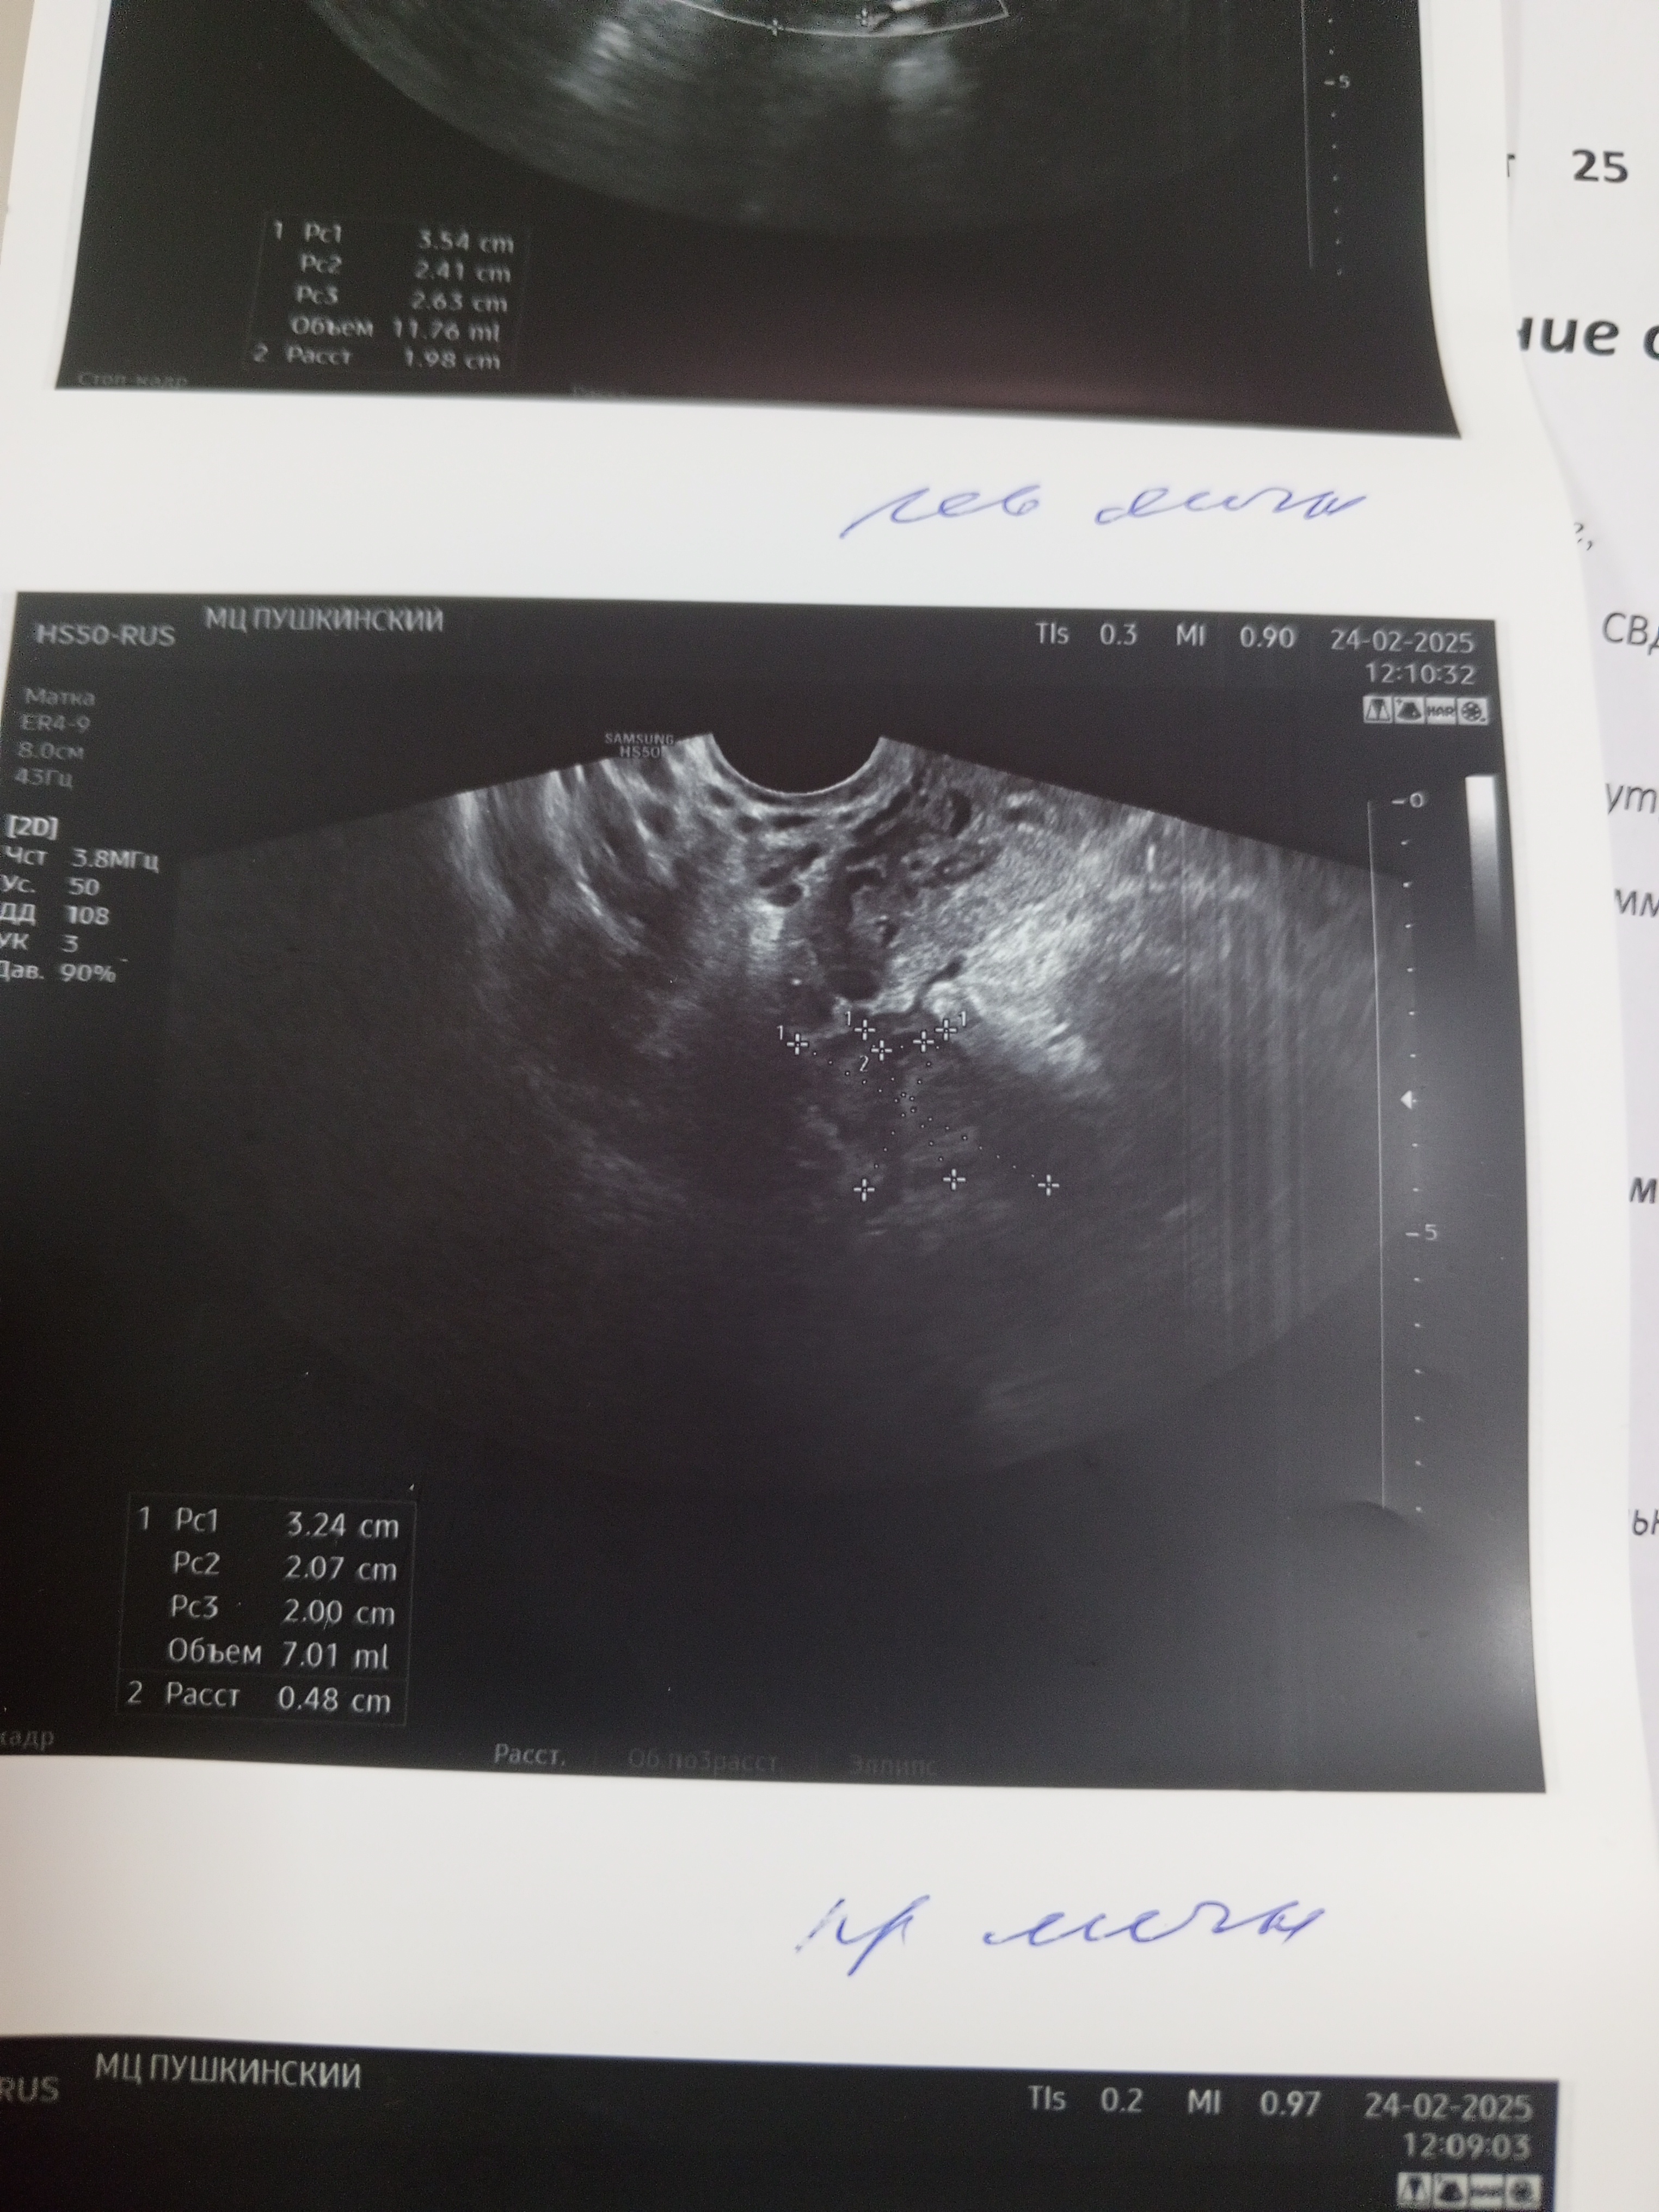

20 дпо это срок 2,6 от зачатия, соответственно 4,6 акушерских УЗИ соответстветствует сроку